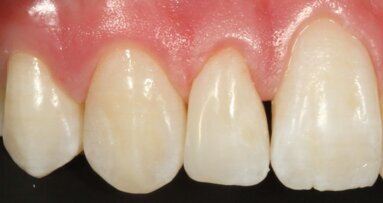

De vraag van veel tandartsen naar een kleiner kleurenpalet wordt steeds meer vervuld. Tokoyuma Dental ging een stap verder met de invoering van OMNICHROMA: ...